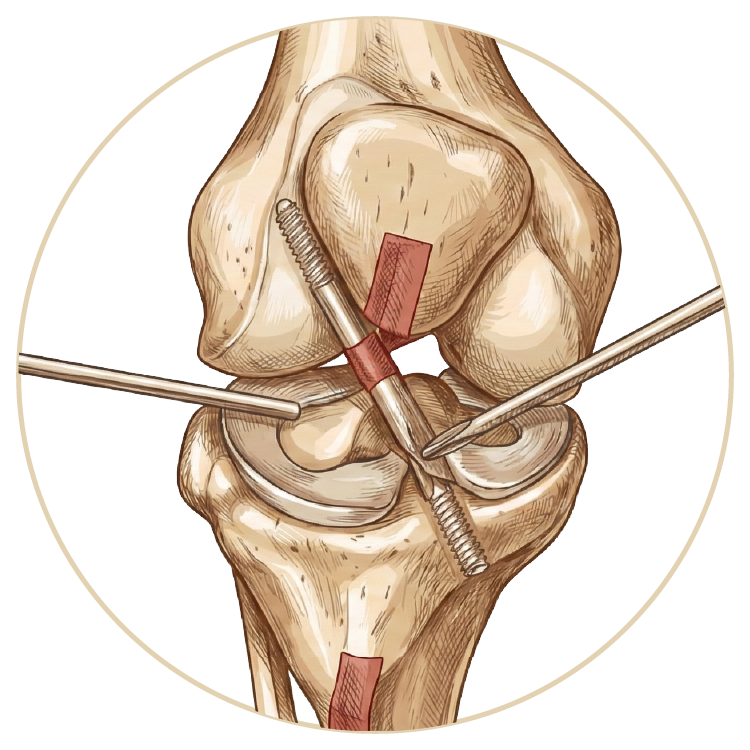

Ön Çapraz Bağ Ameliyatı

Arka Çapraz Bağ Ameliyatı